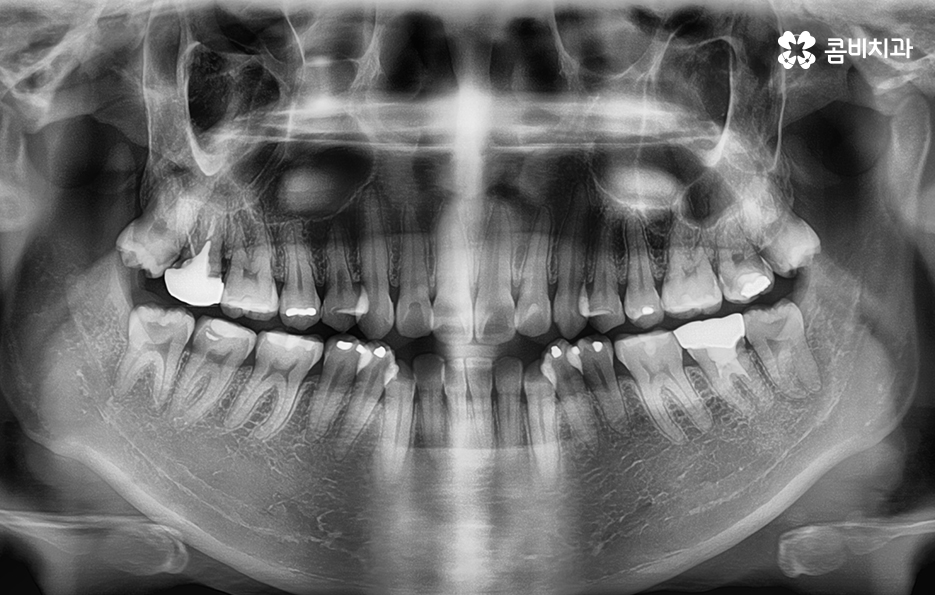

(좌) 얼굴을 고려하여 돌출입을 개선하는 치료 계획을 세움, (우) 사랑니 발치와 상악 14,24 / 하악 34,44 치아 발치 진행

심한 돌출입은 아니었기 때문에 비수술적인 방법으로 치료 진행

치열과 골격 상태에 따라서 비발치, 비수술적인 방법으로 진행이 되는 경우도 많고

돌출입이나 부정교합이 심한 경우에는 발치와 함께 양악 수술이 병행되어야 하는 경우도 있습니다.